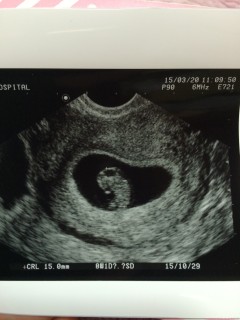

赤ちゃん15.0mm。 無事心拍確認!母子手帳ももらって来てくださいと言われ一安心! つわりはまだ軽いので上の子とまったりマタニティーライフすごします♡

CRL15㎜、心拍確認できて無事母子手帳もらえました!